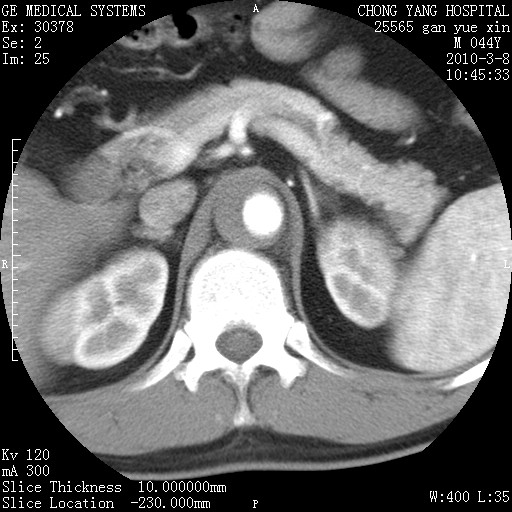

标题: CT24940:主动脉增强,典型病例。 [打印本页]

标题: CT24940:主动脉增强,典型病例。

夹层动脉瘤。

动脉夹层

夹层动脉瘤,典型

主动脉夹层。

动脉夹层的分型:

⒈debakey分型:根据主动脉夹层累及部位,分为三型:ⅰ型:原发破口位于升主动脉或主动脉弓部,夹层累及升主动脉、主动脉弓部、胸主动脉、腹主动脉大部或全部,少数可累及髂动脉。ⅱ型:原发破口位于升主动脉,夹层累及升主动脉,少数可累及部分主动脉弓。ⅲ型:原发破口位于左锁骨下动脉开口远端,根据夹层累及范围又分为ⅲa,ⅲb。ⅲa型:夹层累及胸主动脉。ⅲb型:夹层累及升主动脉、腹主动脉大部或全部。少数可累及髂动脉。

⒉stanford分型:a型:夹层累及升主动脉,无论远端范围如何。b型:夹层累及左锁骨下动脉开口以远的降主动脉。

夹层动脉瘤,少量胸水

夹层动脉瘤;左侧少量胸腔积液。

典型主动脉夹层。